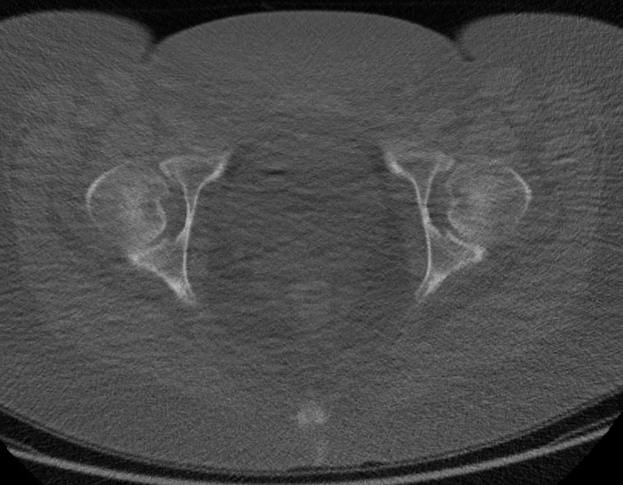

Eine Schwarz-Weiß-MRI-Aufnahme des Abdomens eines Mannes, die sich auf die Prostata konzentriert und detaillierte anatomische Strukturen zeigt.